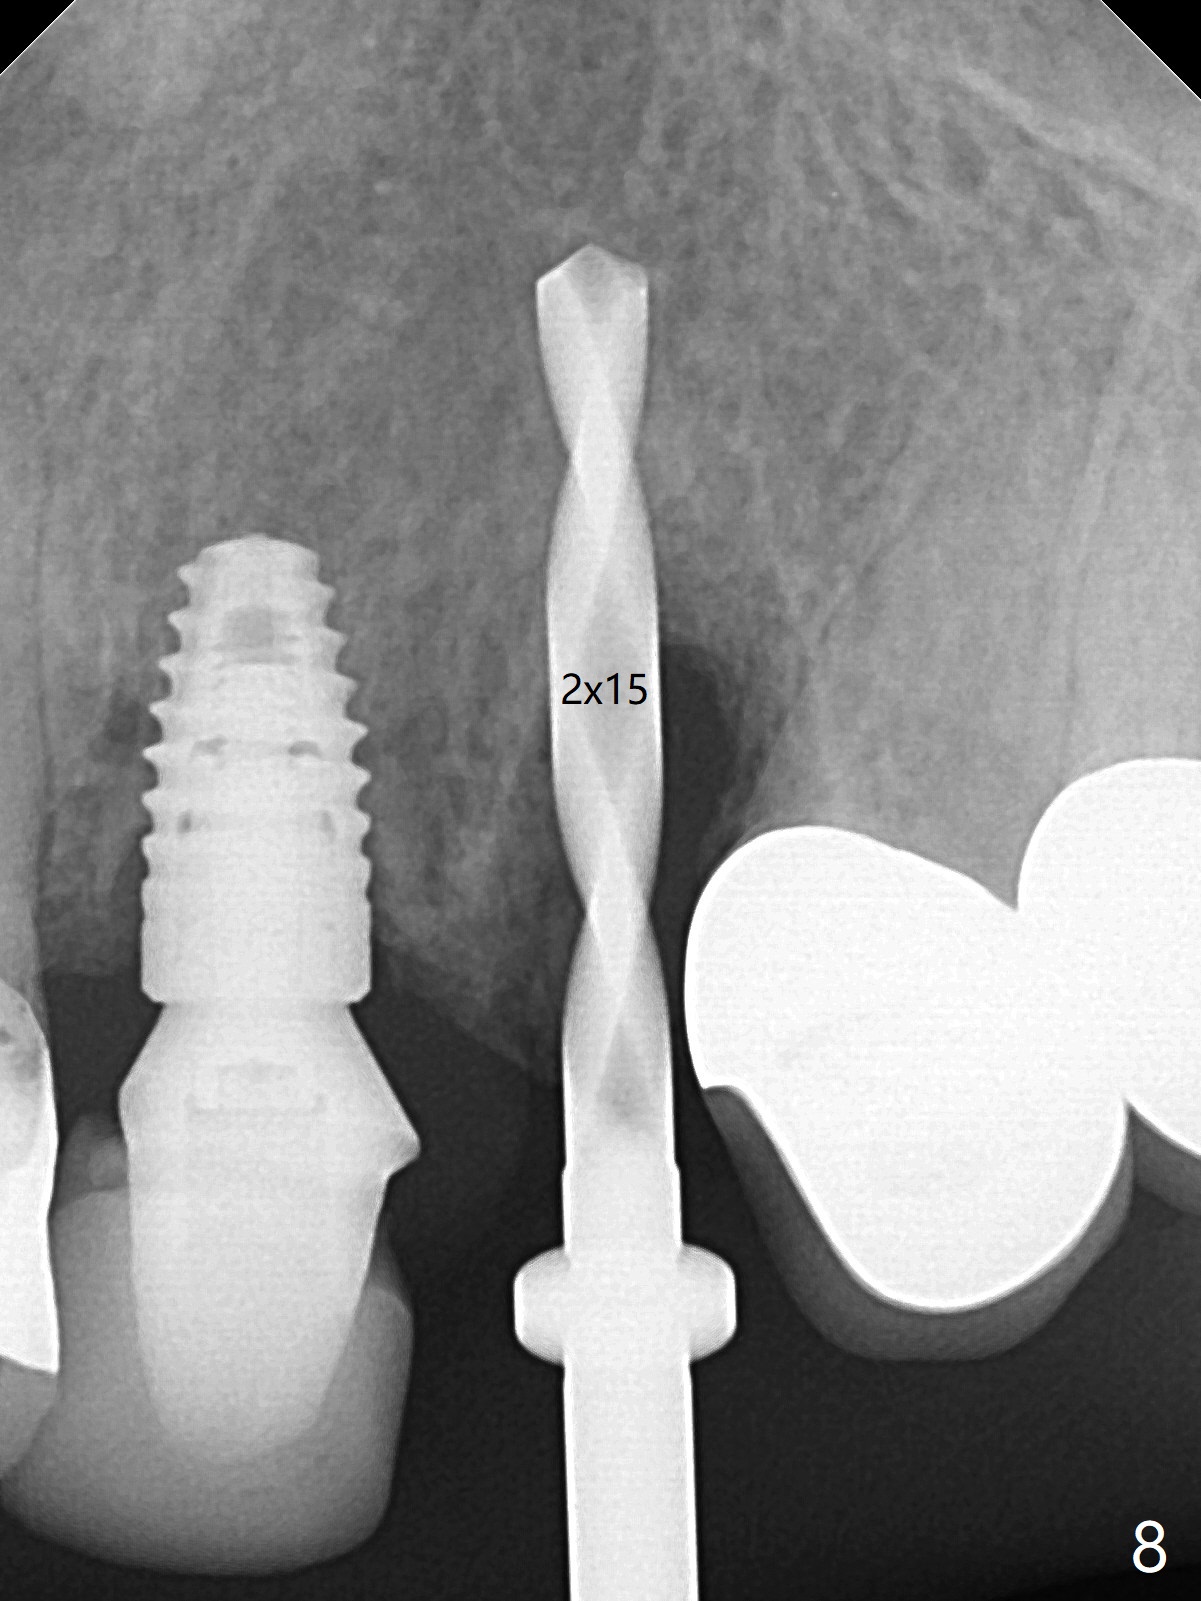

左上尖牙拔除前发现远中腭侧瘘道,拔除后发现相对牙槽嵴骨缺损(图一(术前CT):*),其实患牙根尖在颊侧骨板颊侧(图二:>),拔除后,根尖骨板缺损(图三:>),由于后者离颊侧牙槽嵴(图四:红箭头)远,骨粉修复重要性不如腭侧牙槽嵴(图四:白箭头),当窄植体植入后(图四:绿色),首先在腭侧植骨(图五:红圆圈),因为基台放置后(图六:粉红色),腭侧植骨开口狭窄(图六:白箭头)。即刻种植总是腭侧,颊侧间隙大,颊侧根尖缺损填骨应该容易(图七:橘黄色圆圈),即使不全(*),无关大局。徒手初步钻洞(图八),种植(图九)方向尚可,植骨好像完全(图十:*)。术后一周临时牙冠(11,尖牙)比侧切牙还短(图十一),随着愈合,尖牙牙冠会比双尖牙还短,因为植体偏腭侧,可能需要调整临时牙冠边缘。颊侧牙龈单纯疱疹感染,颊侧根尖仍有疼痛,腭侧瘘道缩小。